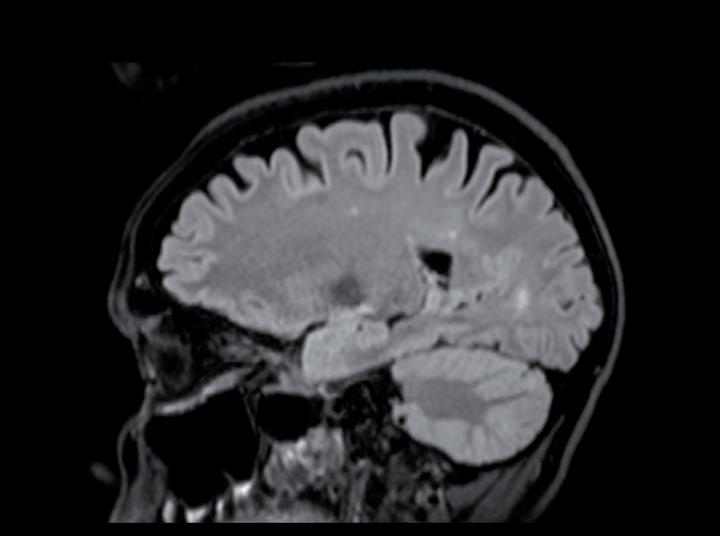

In considerazione della sintomatologia riferita dalla paziente con sensazione di rigidità nucale, difficoltà ai movimenti, dolore base collo, instabilità nella marcia,

parestesie arti inferiori e ipostenia estremità distali esacerbate dal movimento, previa valutazione Multidisciplinare, si completava con RM encefalo + rachide mdc in data 18/07/2023. L’esame confermava la progressione a livello cerebellare destro con comparsa di multiple nodulazioni leptomeningee di natura ripetitiva a livello di tronco encefalico, nervi cranici, superficie midollo spinale, radici cauda e sacco durale (figure 1-3).

Figure 1, 2 e 3. RM encefalo-tronco encefalico-rachide MDC basale pre-trattamento con T-DXd.